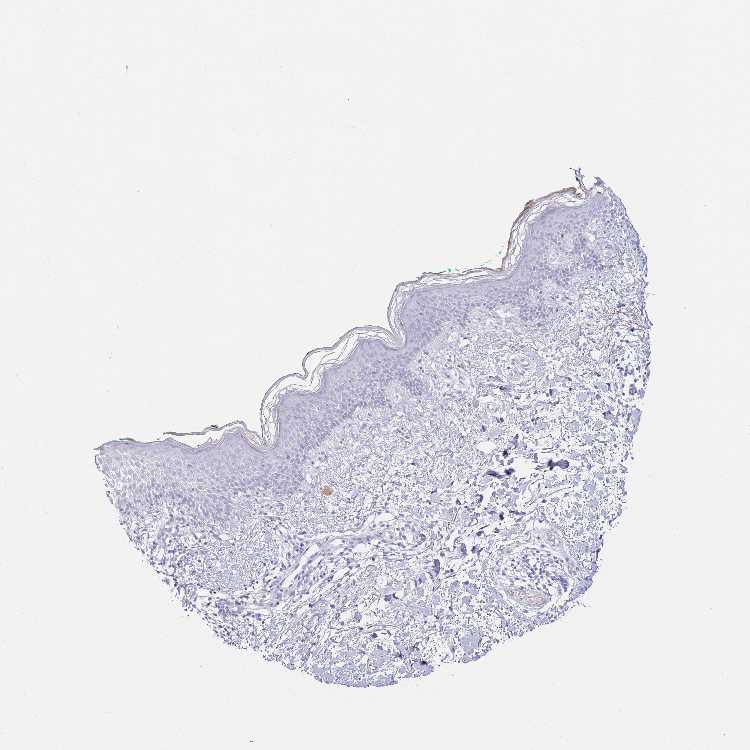

SKIN 2 - Antibody stainingi

Antibody staining in the annotated cell types in the current human tissue is reported as not detected, low, medium, or high, based on conventional immunohistochemistry profiling in selected tissues. This score is based on the combination of the staining intensity and fraction of stained cells.

Each image is clickable and will lead to virtual microscopy that enables deeper exploration of all samples and also displays staining intensity scores, fraction scores and subcellular localization as well as patient and tissue information for each sample.

Antibody HPA045728

Epidermal cells Not detected